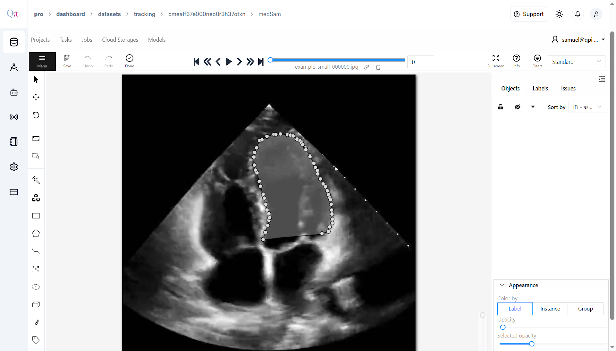

- On the displayed image, click to place points around the target area, forming a polygon that outlines the region of interest.

- Ensure that each polygon corresponds to the classes you defined during dataset creation, providing accurate visual prompts for segmentation.

- Continue to draw polygon points for the classes you want to annotate manually.

Save Manual Annotations & Start Inference

Once your manual annotations are complete, click âSAVEâ to store them in the system.

After saving, click âStart Inferenceâ.

MedSAM2 will automatically run inference on the entire dataset using the visual prompt you provided on the first frame.